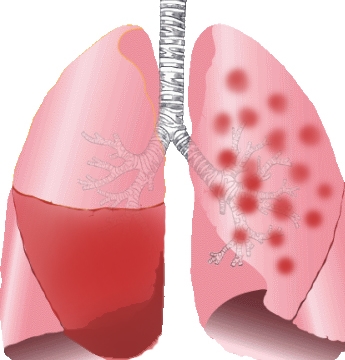

감기 발생 부위는 주로 코나 목 등 상기도가 원인 미생물이 감염되어 염증이 발생하는 것입니다. 이와 달리 폐렴 그 중 일반적인 폐렴의 경우는 폐 속의 감염으로 폐포라는 부위에 염증이 발생한 것을 말합니다.

폐포란 산소를 받아들이고 이산화탄소를 배출하는 호흡을 하고 있는 부분입니다. 따라서 이 폐포에 염증이 있으면 숨 쉬기가 힘들고 괴로우며 호흡이 빨라지고 가끔은 호흡곤란에 이르기도 합니다. 그리고 입원이 필요할만큼 중증이 되기도 있어서 미리 그 둘의 차이를 구분해야 합니다.

발생 부위는 폐이며 중증의 경우는 입원이 필요합니다. 전형적인 증상은 대부분은 38도 이상의 고열과 기침, 노란색이나 녹색 가래, 숨가쁨, 가슴통증 등이 있습니다. 특히 가래 색깔은 폐렴 구균감염증은 적갈색 즉 녹슨 색깔의 가래를 볼 수 있습니다.

폐렴 원인은 폐렴구균, 인플루엔자균 등의 세균과 라이노바이러스, 인플루엔자바이러스, RS바이러스, 파라인플루엔자바이러스, 코로나 바이러스 등이 있습니다.